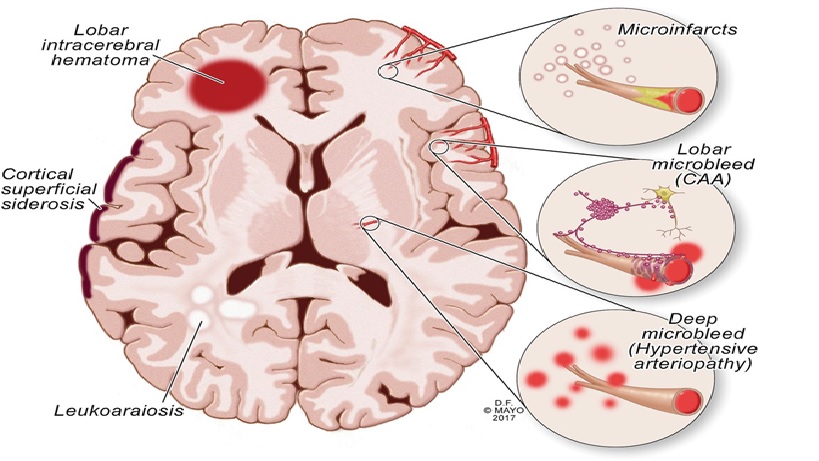

Cerebral amyloid angiopathy (CAA)

CAA là sự thâm nhiễm màng não mềm và xâm nhập vào các mạch máu vỏ não của amyloid, chừa các vùng dưới vỏ não và hệ thống mạch máu (infiltration of leptomeningeal and penetrating cortical vessels with amyloid, sparing the subcortical regions and the systemic vasculature)

- Xảy ra với tần suất tăng sau sáu mươi tuổi

- Biểu hiện lâm sàng chính của CAA là xuất huyết nội sọ thùy, có thể là lẻ tẻ hoặc di truyền.

- CAA cũng có liên quan đến lão hóa bình thường, bệnh Alzheimer, nhồi máu não và mất myelin quanh não thất.

- Các nghiên cứu sinh hóa đã chỉ ra rằng tích tụ amyloid (amyloid deposits) trong não của bệnh nhân bị lão hóa bình thường, xuất huyết liên quan đến CAA lẻ tẻ (sporadic CAA-associated hemorrhage), xuất huyết não di truyền(hereditary cerebral hemorrhage) và bệnh Alzheimer là giống nhau.

- Cơ chế chính xác mà CAA tạo ra xuất huyết thùy và vai trò của CAA trong sự phát triển của chứng mất trí nhớ là không rõ ràng.

- Sinh thiết vỏ não liên quan và leptomeninges là cách duy nhất để chẩn đoán CAA.

- Điều trị cấp của xuất huyết thùy liên quan đến CAA bao gồm kiểm soát tích cực tăng huyết áp liên quan và chăm sóc hỗ trợ.

- Phẫu thuật chưa được chứng minh là cải thiện khả năng sống sót.

- Nên tránh dùng thuốc chống tiểu cầu và thuốc chống đông máu ở bệnh nhân cao tuổi mắc CAA.

Deep hypertensive hemorrhage vs Lobar (amyloid ) hemorrhage